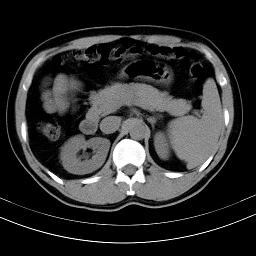

标题: CT18388:肝脏膈肌间隙内大量脂肪密度影 [打印本页]

标题: CT18388:肝脏膈肌间隙内大量脂肪密度影

是脂肪不是气体,有时候会碰到这样的病人,脂肪过多吧。

腹腔脂肪沉积过多

膈下脂肪沉积。

考虑膈下脂肪沉积。

激素治疗的病人容易脂肪沉积